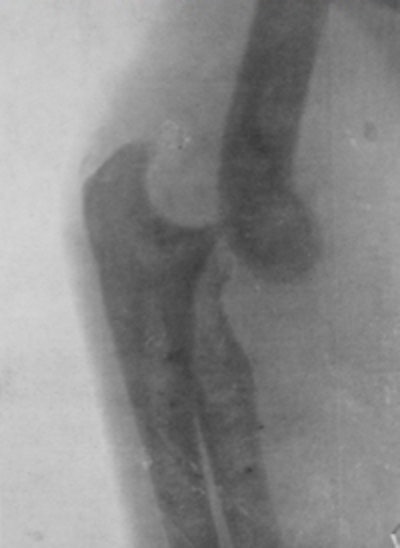

Early radiograph obtained at the Royal Free Hospital in London.

The Stobart Hospital had 100 beds, was located in an old concert hall, and was established before the "official" British Army hospitals had been set up. On 8 October 1914, they were under shellfire for 18 hours and their situation was desperate. They evacuated their patients, then started to walk to Holland and were picked up by three London buses and had to sit on ammunition cases. Stoney escaped from Antwerp only 20 minutes before the bridge was blown up. She continued work in France at the Chateau Tourlaville near Cherbourg. Radiography was used to show the positions of the fractures and the location of the shrapnel and bullet that could then be extracted.